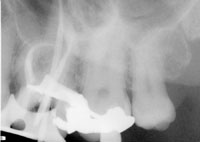

In the following case, the author used several of the above suggestions to properly determine working length. This tooth was diagnosed with irreversible pulpitis, and multiple visits were required to complete the case. While the maxillary sinus and zygoma often interfered in the author’s interpretation of the tooth’s anatomy, the tooth’s anatomy itself proved to be the largest obstacle to performing ideal root canal therapy (Figure 1). Originally, a periapical radiograph was taken to determine if the mesial canals actually curved as severely as the hand files had indicated. A periapical radiograph was then taken to approximate the measurements (Figure 2). Just from his own tactile sensation, the author came close to approximating the proper length of the canals but was not entirely accurate.

Figure 1 Preoperative radiograph demonstrating complex anatomy.